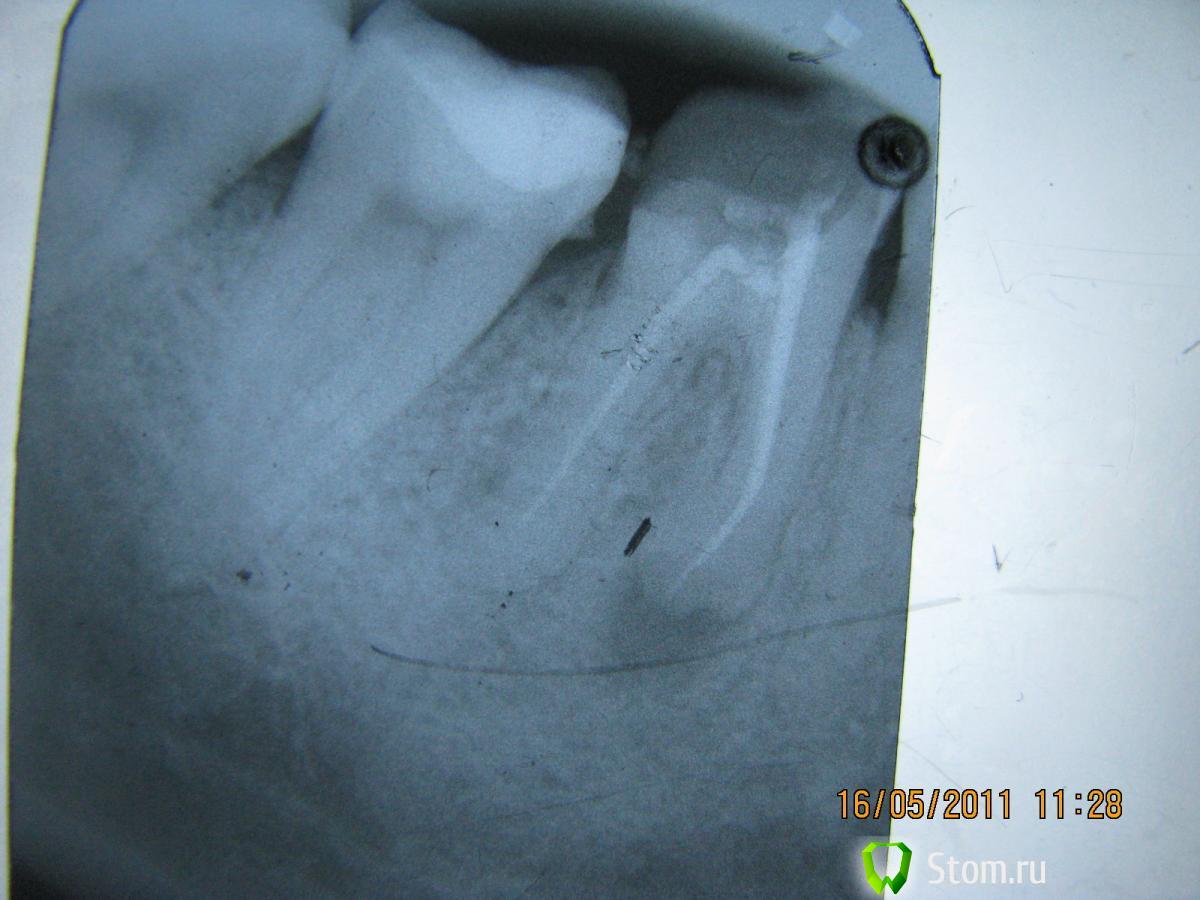

Elenushka Опубликовано 13 января, 2012 Автор Поделиться Опубликовано 13 января, 2012 Вот представляю вашему вниманию пациента.На зубах 45- 47 с 1994 года по 2010г находился металло-керамический мост. НИчего его не беспокоило. Пришел с целью заменить конструкции.(сразу оговорка- он категорически против удаления зубов, денег на эксперименты не жалеет)))Сделала снимок и увидела- перфор, сделанный давным давно,кости как- то маловато. Ну вообщем предлагала удалить, ни в какую. Он мой хороший знакомый, поэтому принялись экспериментировать. 47зуб- был под вкладкой много лет не стали трогать. Вообщем в одно вмешательство- откинут слизисто- надкостничный лоскут, все зачищено, перфор отпрепарирован. Закрыт цементом. Дефект заполнен костью,прикрыт мембраной. Все ушито. следующий снимок сделан совсем недавно( спустя чуть больше 10 месяцев. Запротезирован( мк мост с круговой гирляндой) Снимок работы позже(он в отъезде).В общем на снимочке все так себе вроде бы, а во рту все очень прилично выглядит. Ссылка на комментарий

светляк Опубликовано 15 января, 2012 Поделиться Опубликовано 15 января, 2012 Здравствуйте,коллеги.Не знаю,можно ли назвать экспериментом мой случай или все-таки желание сохранить зуб...: Молодая девушка. Зуб 46-резорциненный-не беспокоил,но коронковая часть разрушена почти полностью(если не учитывать старую ,ужасную пломбу без намека на всякую анатомию).На снимке-резорбция медиальных корней.Конечно,с моей стороны последовало предложение удалить зуб и не рисковать,но пациентка пожелала рискнуть("удалить всегда успею"). И с согласия пациентки со всякими расписками о безгарантийном лечении мы начали лечение,которое продолжалось где-то 4 месяца.Была проведена эндодонтия,заложен каласепт и меняла я кала септ на протяжении лечения 3 или 4 раза.Через 4 месяца,увидев,что разрежение уменьшилось,я запломбировала каналы окончательно.Затем-культевая вкладка и коронка. Вложения-приличные.Но иначе восстановить не получилось бы. Ссылка на комментарий

светляк Опубликовано 15 января, 2012 Поделиться Опубликовано 15 января, 2012 Коллеги,извините,за качество.Ну не очень я дружу с отправкой снимков... Смотреть снимки надо в такой последовательности: 1-5-6-2-3-4. Ссылка на комментарий